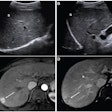

The researchers set out to test both reading methods to establish their effects on radiologist accuracy and variability. They also wanted to assess the system's performance compared with radiologists. Three radiologists -- with three, more than 10, and more than 20 years of breast ultrasound experience, respectively -- used the Koios DS software to review 500 pathology-proven breast ultrasound studies. After rendering an initial diagnosis, they were immediately presented with the software's analysis and could change their diagnosis. Four weeks later, the radiologists again read the cases, but this time concurrently with the software's analysis.